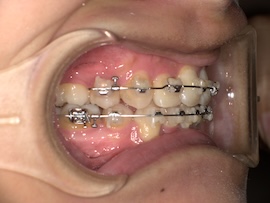

前回から1ヶ月後の歯並びはこんな感じです。

そこから1ヶ月後、

さらに1ヶ月後、